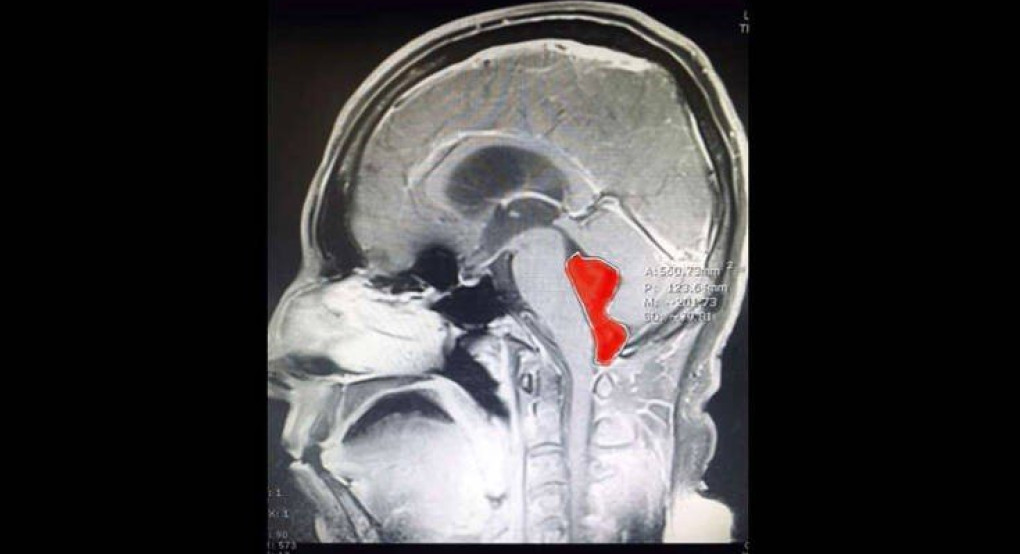

Η μαγνητική υπέδειξε μια κύστη στην τέταρτη κοιλία, πίσω από τον προμήκη μυελό και τη γέφυρα. Το ιατρικό team του κέντρου Ascension Seton του Τέξας ανάλαβε τη δύσκολη επέμβαση, καθώς η κύστη αποδείχτηκε τελικά πως ήταν το παρασιτικό σκουλήκι ταινία, μήκους 4-5 εκατοστών.

Το οποίο ήταν εκεί «τουλάχιστον 10 χρόνια». Ο Dr Jordan Amadio του Ascension Seton θεωρεί πως η ταινία πέρασε από μολυσμένη με αυγά ταινίας τροφή στον εγκέφαλο του Gerard, όπως αναφέρεται ο ασθενής (χωρίς επίθετο).